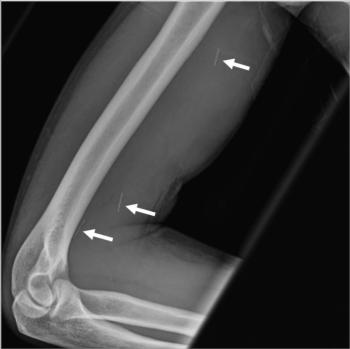

Figure 1. 37-year-old man with history of broken needle proximal to the right elbow while injecting heroin. Anterior-posterior X-ray view of the right humerus shows three linear hyperdensities in the soft tissues of the arm (arrows).

High-res (TIF) version